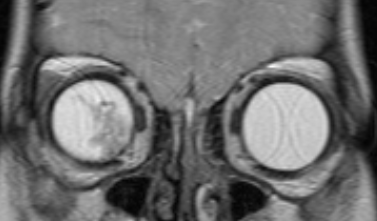

- D - рассеянные опухоли с крупными опухолевыми массами, разнокалиберными отсевами в стекловидном теле и/или субретинальном пространстве в более чем 3 мм от новообразования с субретинальной жидкостью более 6 мм от образования, включая полную отслойку сетчатки (рис. 3 и 4).

![Визуализация ретинобластомы с помощью МРТ. Фронтальное изображение орбит. Клиническая группа D]()

Рис. 4. Визуализация ретинобластомы с помощью МРТ. Фронтальное изображение орбит. Клиническая группа D